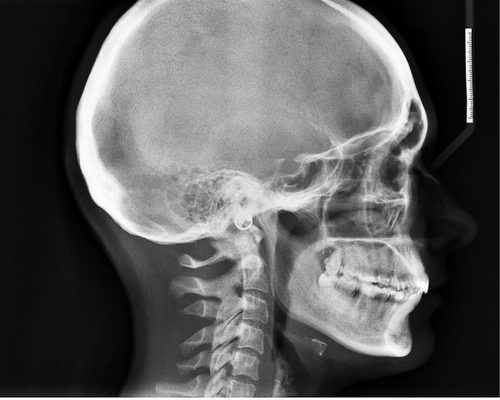

Одна из причин, уходящая корнями в ваше глубокое детство, – родовая травма, нехватка кислорода у плода. В этом случае могло произойти смещение шейных позвонков, один из которых слегка пережимает проходящий рядом сосуд с кровью. Таким образом, нарушается кровоснабжение на одном из участков головного мозга, следствием чего является головная боль, чаще всего заявляющая о себе в области висков, лба и темени.

Она может быть и последствием травм и ранений черепа, головного мозга, когда из-за ушиба нарушается отток жидкости из полостей желудочков мозга, возникает повышенное внутричерепное давление, нарушается приток-отток крови. Следствие – головные боли.

Очень сильные головные боли могут быть признаком растущей опухоли головного мозга и нередко сопровождаются потерей сознания, двоением в глазах, рвотой. Это происходит за счет сдавливания опухолью сосудов и полостей желудочка мозга.

Затылочная боль и боль в верхнем отделе шеи — очень неприятная боль уже потому, что трудно определить, что же на самом деле болит — голова или шея. Среди всех неисчислимых возможных причин головной боли, существует и та, которая провоцируется напряжением глубоких разгибателей шеи, располагающихся прямо под затылком.

— заболевания шейного отдела позвоночника (спондилит, подвывихи в мелких межпозвонковых сочленениях, растяжение при травме, остеохондрозе) боль чаще локализуется в затылочной части головы и в шее и может усиливаться при движениях головы.

Боль в затылке вследствие остеохондроза

Если болит шея и затылок. причины могут быть в наличии такого заболевания, как остеохондроз шейного отдела позвоночника. Заболевание проявляется в разрушении дисков шейных позвонков, а боли при этом проявляются постоянно и ощущаются не только в шее и затылке, но и в висках. Они становятся интенсивнее при движениях головой и могут сопровождаться:

- шумом в ушах;

- тошнотой;

- нарушениями координации;

- пеленой перед глазами и двоением.

Боль в затылке при повышенном внутричерепном давлении

Повышение внутричерепного давления характеризуется:

- давящими, распирающими болями в затылочной области или по всей голове;

- усилением болей при ярком свете и громких звуках;

- тяжестью в голове и болью в глазных яблоках;

- рвотой, которая не снижает болевые синдромы.

Диагностика боли в затылке

Помимо сбора анамнеза о характере, времени и интенсивности боли, диагностика может включать:

- осмотр врачом;

- измерение артериального давления, его мониторинг;

- ультразвуковое исследование;

- электроэнцефалографию;

- магнитно-резонансную томографию ;

- исследование глазного дна окулистом .

В случае если имеется подозрение на наличие опухоли мозга, потребуется консультация нейрохирурга.